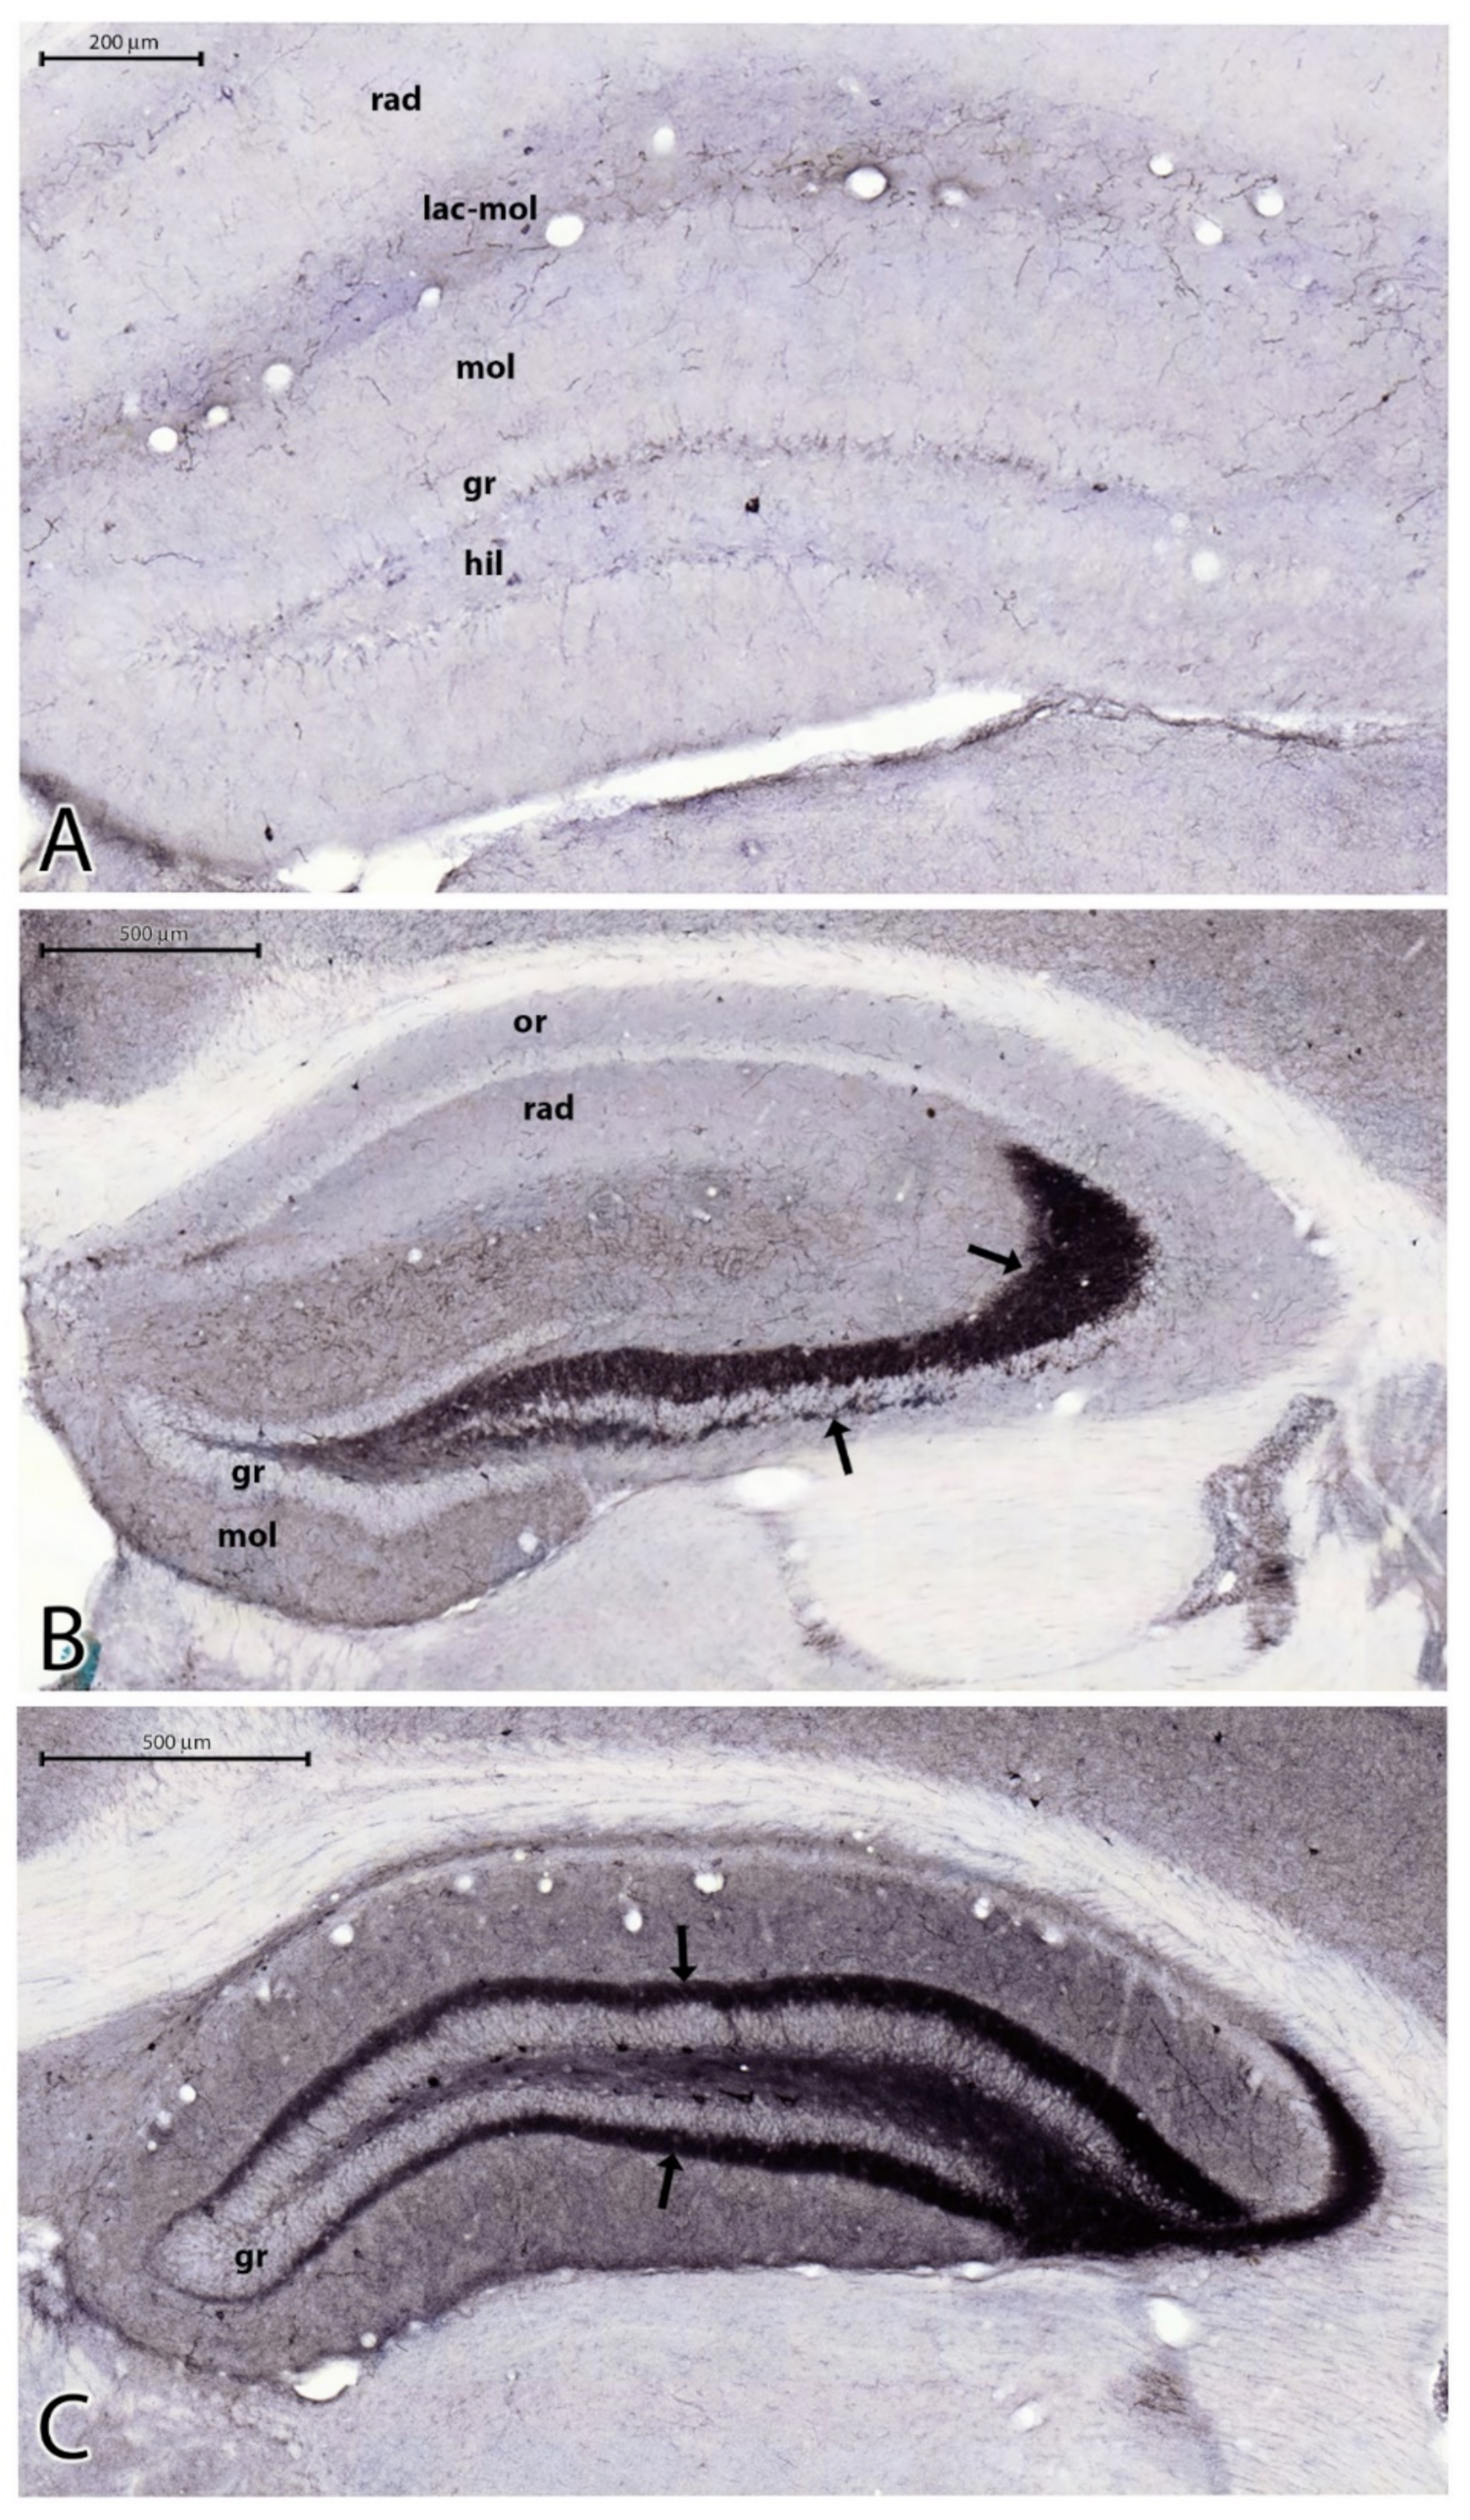

2.3. Sprouting of Mossy Fibers 3.5 Months after the SE

3.3. Sprouting of Mossy Fibers in the Epileptic Mice